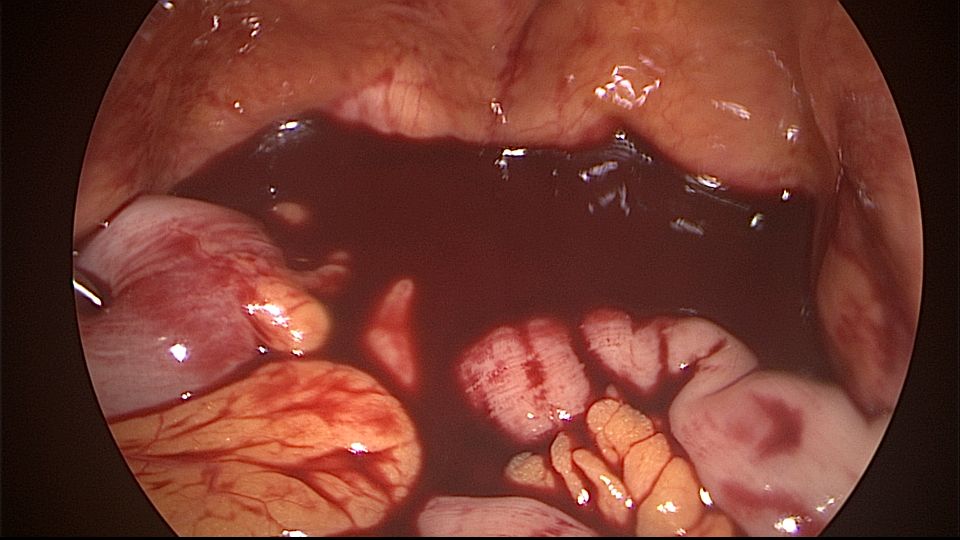

患者54岁,G1P1,顺产1次。安环33年,绝经3年,外院取环失败,子宫穿孔,盆腔积血。子宫后位,宫腔镜见宫颈管组织杂乱,宫颈管上段前壁不规则潜行假道,假道后侧寻找到宫颈内口。扩张宫颈内口,进入宫腔,见O型环位置正常,异物钳取出节育环,宫腔内看不到子宫穿孔。腹腔镜见盆腔积血约400ml,子宫前壁中段偏左见直径0.5cm不规则穿孔,少许渗血,缝合修补子宫穿孔。因左侧卵巢囊肿,患者及家属要求切除双侧附件。